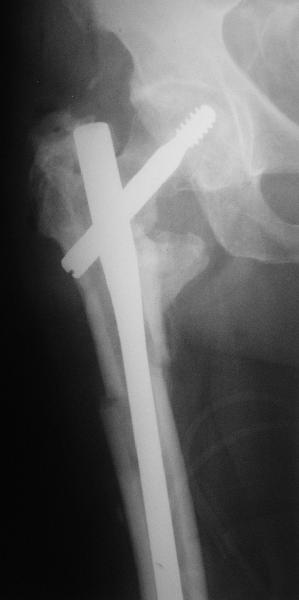

На прошлой неделе оперировали похожего пациента. 2 года после неудачного остеосинтеза PFN в другом регионе. После удаления остатков железа выявилось несращение вертельной области.

Поскольку в нашем случае выявилась подвижность, мы наложили дистрактор таз-бедро на 3 дня, и сделали остеосинтез гаммой без остеотомии. То, что произошла "корригирующая остеоклазия" в подвертельной области, выявили после введения гвоздя. Пациент уже уехал домой, будем наблюдать.